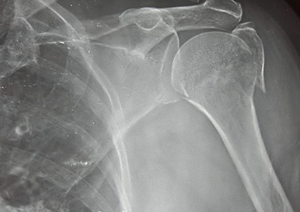

Case:2 Fracture of Neck Humerus with Fracture of Greater Tuberosity

Pre-Op AP

Pre-Op Trausaxillay